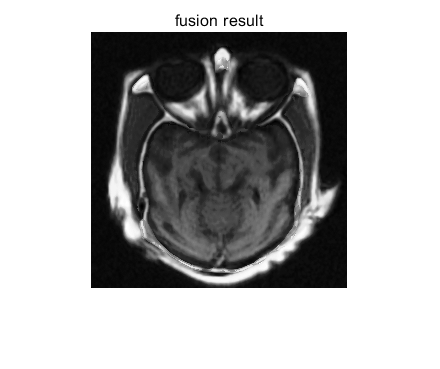

医学图像融合是指将不同模态医学影像(如 MRI、CT、PET)的互补信息整合为单幅图像,以提升临床诊断与治疗规划的准确性。其中,MRI(磁共振成像)与 CT(计算机断层扫描)的融合是临床最常用的组合之一,广泛应用于肿瘤诊断、神经外科手术规划、骨科植入评估等场景:

理想的 MRI-CT 融合需满足信息完整性(保留双方关键特征)、空间一致性(无几何错位)、视觉清晰度(无伪影) 三大核心需求,传统融合方法(如简单加权、金字塔分解)难以平衡多模态图像的特性差异,需借助更精准的图像增强与特征提取模型。

⛳️ 运行结果